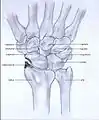

Stages

Post-traumatic osteoarthritis can be classified into four stages.[1][7] These stages are similar between SLAC and SNAC wrists. Each stage has a different treatment.

- Stage I: the osteoarthritis is only localized in the distal scaphoid and radial styloid.

- Stage II: the osteoarthritis is localized in the entire radioscaphoid joint.

- Stage III: the osteoarthritis is localized in the entire radioscaphoid joint with involvement of the capitolunate joint.

- Stage IV: the osteoarthritis is located in the entire radiocarpal joint and in the intercarpal joints. It also may involve the distal radio-ulnar joint (DRUJ).

Stage I

Stage II

Stage III

Stage IV